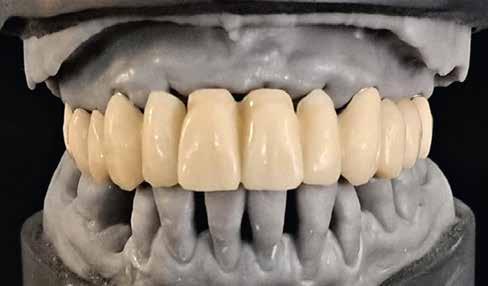

Interdiszciplináris fogászati kezelés myofunkcionális készülék, alignerek és protetikai ellátás alkalmazásával

MED. DENT Abradált frontfogakkal rendelkező felnőtt páciens interdiszciplináris kezelése